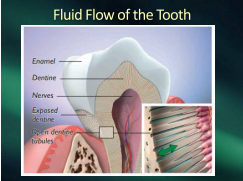

Think of a hand over nose and mouth

that fluid flow must go south

Without a source of nutrient

the tooth suffers punishment

Stopping fluid flow is the way

to develop massive rampant decay

Steinman found the fluid flow

sometimes fast, sometimes slow

Rapid transit brings nutrient

that’s the healthy precedent

He found those metabolic shields

related to what was in our meals

Carbs and protein and ATP

determined the tooth’s destiny

Dentists and parents will understand

that decay is systemic – isn’t that grand

Through diet alone you can bestow

control over that marvelous fluid flow

The secret is in the Parotid gland

he’s the one who gives the command

Fluid flow from pulp through enamel

that’s the way in every mammal